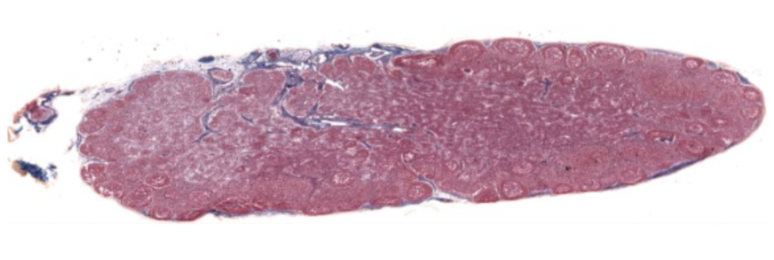

OVARY: Outer cortex, containing follicles at varying stages

Inner medullary region, ovarian artery and veins

simple cuboidal on ovarian surface epithelium in outer cortex

Has basement membrane and DIRCT below as tunica albuginea

Corcles are follicles at varying stages of development

Cortex contains follicles